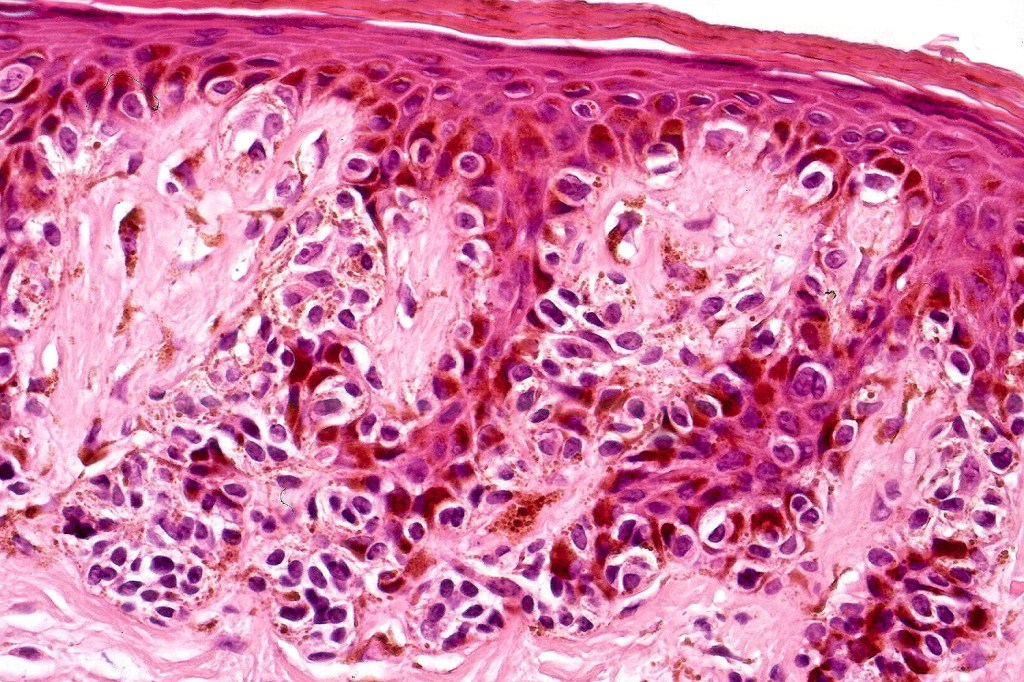

•Cytological atypia- mild, moderate & severe (or more recently, low & high grade (WHO). The problem with the new WHO classification is that mildly dysplastic nevi are now included with the banal nevus category and moderate is low grade and severe is high grade. In all likelyhood, most pathologists will include mild & moderate atypia in the low grade category.

•Variation in the degree of atypia within any one lesion is commonly present

•Rare mitoses

•Pagetoid spread absent

Dysplastic nevus in the majority of cases is instantly recognizable, often at low power. The most important differential diagnosis is obviously melanoma. In junctional lesions, widespread/uniform high grade atypia, frequent mitoses and Pagetoid spread are indicative of in situ melanoma. In compound lesions, dermal nests larger than junctional ones, expansile dermal nests, severe atypia and mitotic activity indicate the presence of melanoma